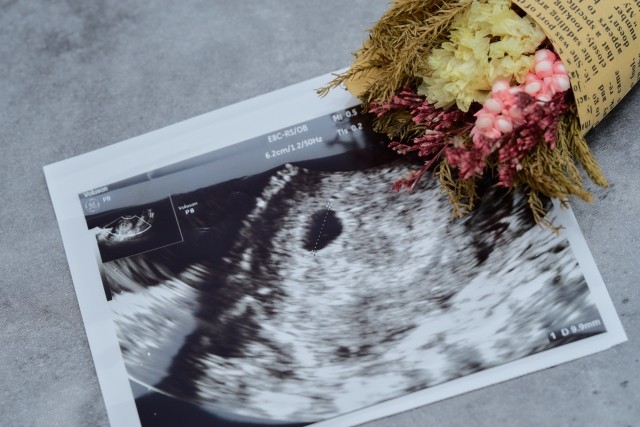

超音波越しとはいえエケチェンを見られる数少ない機会ですので、妊婦さんにとっては単なる「状態確認」の役割を遥かに超える存在でもあります。

毎回、同じような感じで血圧や体重を測ったり尿検査や超音波をやってるだけのようにも見えますが、「何を気にしているか」は週数ごとに案外バラバラだったりします。

この時期に産婦人科医が気にしていることは、主に「子宮内の妊娠か」「流産ではないか」の2点です。

基本的にエケチェンの袋(胎嚢)が見られ始めるのは妊娠5週頃なので、

妊娠6週くらいになっても胎嚢が見えない場合は異所性妊娠の可能性を考える必要があります。(単に月経や排卵時期が乱れているだけのパターンも多いです)

よって、「子宮内に胎嚢が見えた」というのはそれだけで安心材料になります。

よって「心拍が確認できるか」というのは非常に大事。

妊娠5~6週頃だと心拍がギリギリ確認できるかどうかの時期ですが、まずはそこの確認が第一歩になります🐻❄️